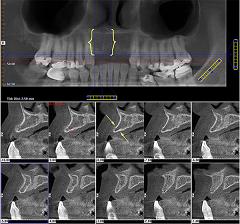

Dependiendo de cada paciente el diagnóstico necesitará una serie de pruebas y estudios complementarios, como pueden ser radiografías, fotos, o modelos de estudio montados en articulador ( este es un dispositivo que simula los movimientos mandibulares).

En algunos pacientes pueden ser necesarias valoraciones concretas dirigidas a diagnosticar alguna patología específica.